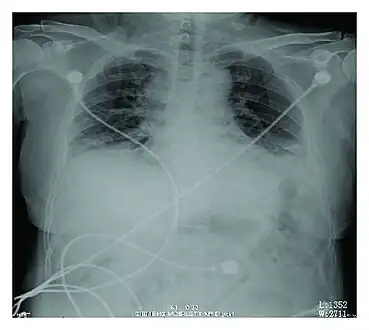

Rapid progression from initial symptoms to respiratory failure is a key feature. An X-ray that shows ARDS is necessary for diagnosis (fluid in the small air sacs (alveoli) in both lungs). In addition, a biopsy of the lung that shows organizing diffuse alveolar damage is required for diagnosis. This type of alveolar damage can be attributed to nonconcentrated and nonlocalized alveoli damage, marked alveolar septal edema with inflammatory cell infiltration, fibroblast proliferation, occasional hyaline membranes, and thickening of the alveolar walls. The septa are lined with atypical, hyperplastic type II pneumocytes, thus leading to the collapse of airspaces. Other diagnostic tests are useful in excluding other similar conditions, but history, X-ray, and biopsy are essential. These other tests may include basic blood work, blood cultures, and bronchoalveolar lavage. The clinical picture is similar to ARDS, but AIP differs from ARDS in that the cause for AIP is not known.

Acute interstitial pneumonia showing a marked reduction in lung capacity -